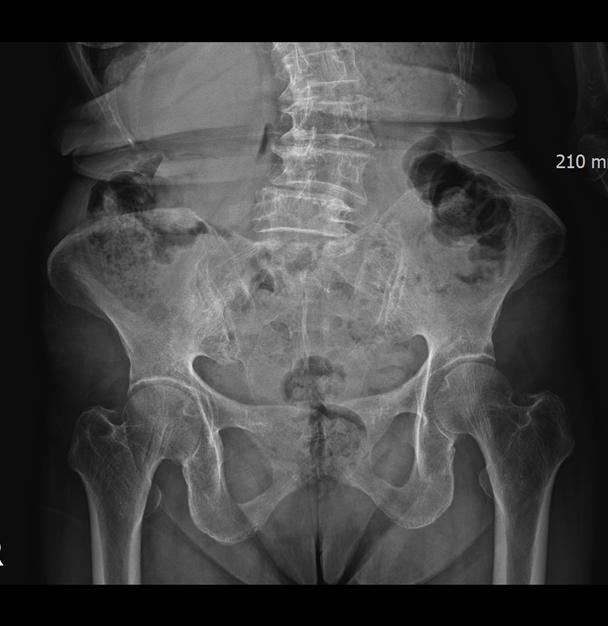

How We Evaluate Pelvic Balance at MADI-BONE CLINIC

At our clinic, pelvic assessment focuses on understanding

the individual’s movement patterns rather than forcing symmetry.

Evaluation may include:

• postural analysis

• pelvic alignment and mobility testing

• hip and lower limb movement patterns

• relationship between pelvis and spine